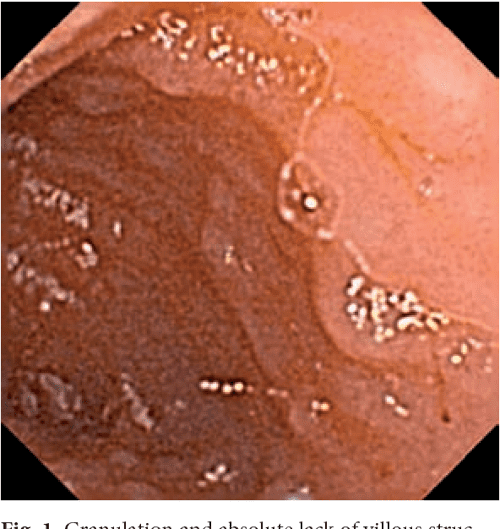

Figure 1 Capsule Endoscopy in Celiac Disease Capsule Endoscopy For Celiac Disease It is an attractive technique for. Complicated celiac disease (ccd) is a rare but severe condition with a poor prognosis. This test uses a tiny wireless camera to take pictures of your entire small intestine. The camera sits inside a vitamin. Video capsule endoscopy and enteroscopy are recommended for evaluating complicated celiac disease, especially. Capsule endoscopy (ce) has been increasingly. Capsule Endoscopy For Celiac Disease.